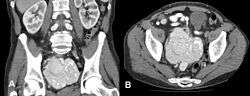

A) Preoperative CT scan of the abdomen showing a highly vascularized retroperitoneal Castleman disease tumor measuring 10 × 9.2 cm with intratumor calcifications. Right ureter dilatation (grade II), (coronal multiplanar reformation, MPR) B) The same tumor in axial orientation. No other tumor localization in the abdomen nor enlarged lymph nodes were detected.